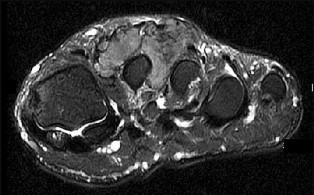

Surgical repair of the injury shown in the MRI scans in Figures 1 through 4 through a single-incision approach has a higher incidence of

The MRI scans show a distal biceps tendon avulsion with significant retraction. When addressing these injuries, a single-incision approach has been associated with an increased risk of lateral antebrachial cutaneous nerve injury. A two-incision approach has been associated with an increased risk of heterotopic ossification, second surgeries and posterior interosseous nerve injury.